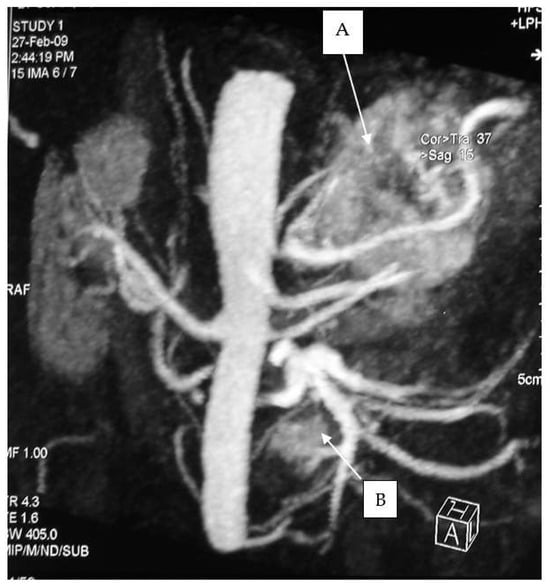

The diagnostic localization of a PCC/PGL is traditionally attempted only once excess catecholamine has been biochemically ascertained [17,18]. Both computed tomography (CT) scanning and MRI are mainstays for adrenal imaging and are used as the primary tests for localizing catecholamine-secreting tumors. CT is the preferred method for its excellent resolution (Figure 3 and Figure 4).

Figure 3. CT scan of an abdominal paraganglioma of above the aortic bifurcation (Zuckerkandl organ’s).